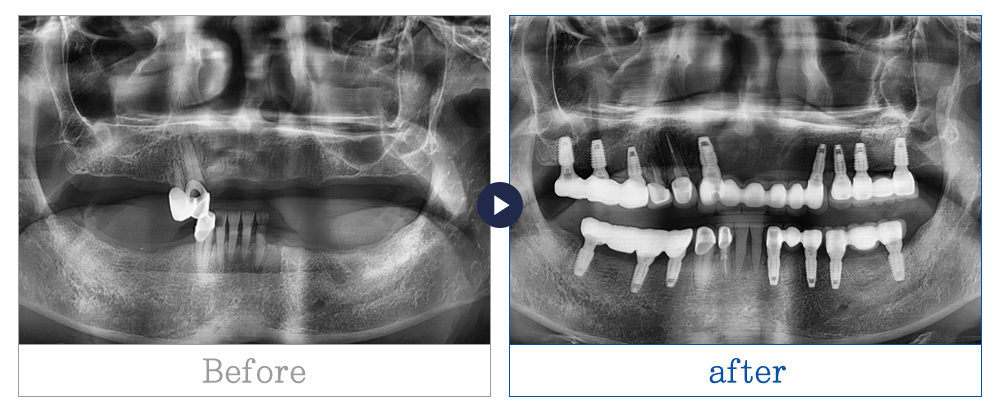

제목 60대중반 남성 카테고리 임플란트

60대중반 남성

치료기간 1년 이상